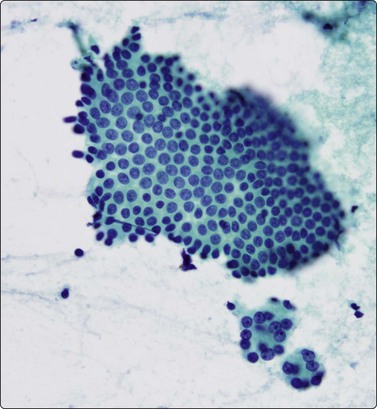

Islet cell tumours (Figs 11.18-11.20)

image image

Fig. 11.18 Islet cell tumor

(A) Poorly cohesive sheets and dispersal; cells with oval nuclei, stippled chromatin and small nucleoli (Pap, IP); (B) Mainly dispersed cells with uniformly round nuclei, speckled chromatin, moderate anisokaryosis; delicate cytoplasm; a suggestion of pseudorosettes (MGG, HP).

image

Fig. 11.19 Islet cell tumor

Criteria for diagnosis

Many single and loosely grouped cells, pseudorosettes,

Rounded monotonous nuclei, mild to moderate anisokaryosis,

Speckled chromatin and 1–3 small nucleoli,

Poorly defined, finely granular cytoplasm, often dispersed in the background,

Nuclei eccentric if cytoplasm intact.

These functional or nonfunctioning tumors of adults are situated mainly in the body and tail of the pancreas. The tumors are well within the scope of EUS cytodiagnosis.114,115 The neoplastic cells are mainly dissociated, but often form loose acinar or follicular clusters and curved or circular rows (Fig. 11.18). In the majority of cases, nuclei are characteristically round to oval and uniformly small. Occasionally, nuclear anisokaryosis may be prominent, but the nuclear chromatin pattern varies little between cells. The chromatin is evenly distributed, coarsely granular or ‘speckled’. The small nucleoli are not easily seen in Giemsa-stained smears. Due to its fragility, the cytoplasm is often dispersed in the background. When it is preserved, nuclei are eccentrically situated within defined cell borders. A very fine, red granularity is often discernible in MGG smears with high magnification. Clumps of amyloid may occasionally be seen, but necrosis is not observed.113,116-119 The cytological pattern of most islet cell tumors is sufficiently characteristic to be easily distinguished from that of pancreatic adenocarcinoma. Production and secretion of specific hormone products cannot be distinguished on the basis of routine cytological smears alone. If the secretory products of the neoplastic cells can be identified by immunocytochemical methods, a more specific diagnosis can be made with confidence. General neuroendocrine markers will usually be positive, such as neuron-specific enolase, synaptophysin, chromogranin-A, PGP9.5 and CD56. Specific secretory products, e.g. insulin can be marked by appropriate antibodies but this does not necessarily correlate with raised serum levels. Electron microscopy will demonstrate dense-core neurosecretory granules. A decision on whether a tumor is benign or malignant is problematic. Even histopathology is poorly predictive of aggressive behavior. In general, nuclear atypia and pleomorphism cannot be relied on as cytological criteria of malignancy (Fig. 11.20). More aggressive behavior correlates with a raised proliferation index assessed using Ki-67 immunohistochemistry (> 2%).120 This is a parameter in the WHO 2004 histology based-grading system.121,122 Only documentation of metastasis finally provides proof of malignancy.123,124